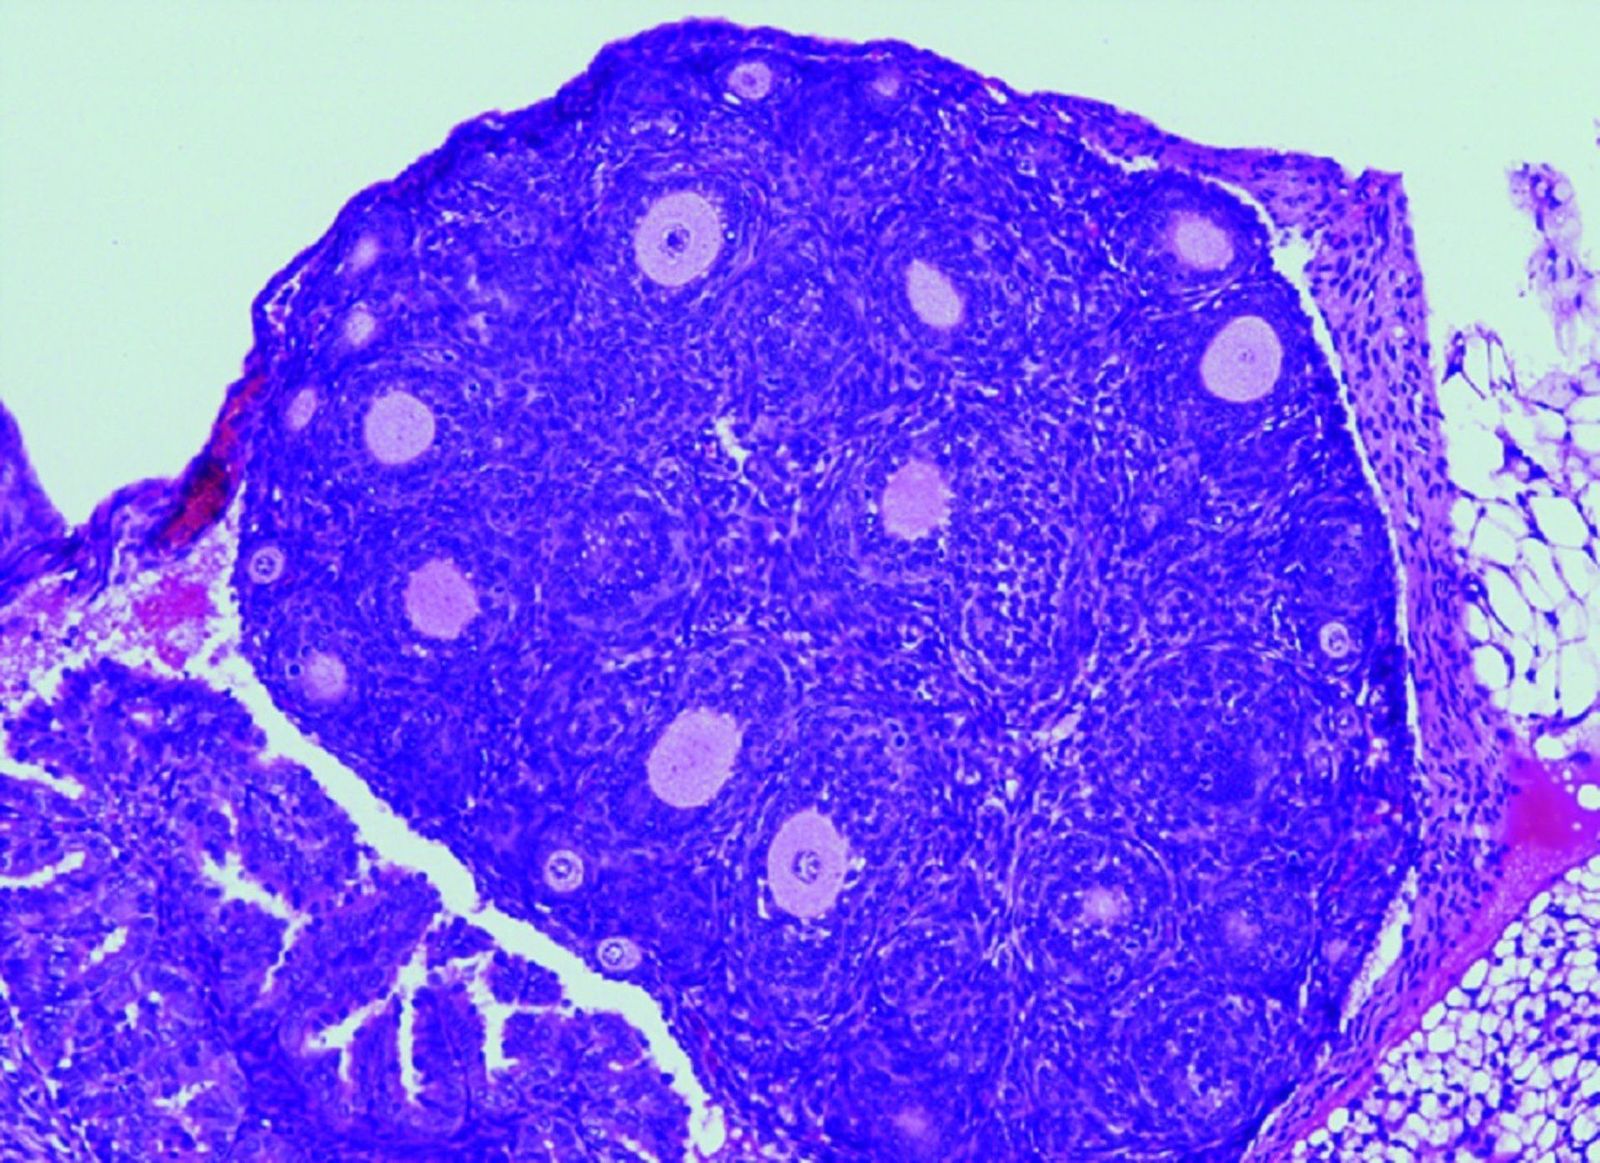

Reducción en el número de folículos ováricos (causante de la insuficiencia ovárica prematura) en los ratones con la variante humanizada en FOXL2. - CSIC-USAL